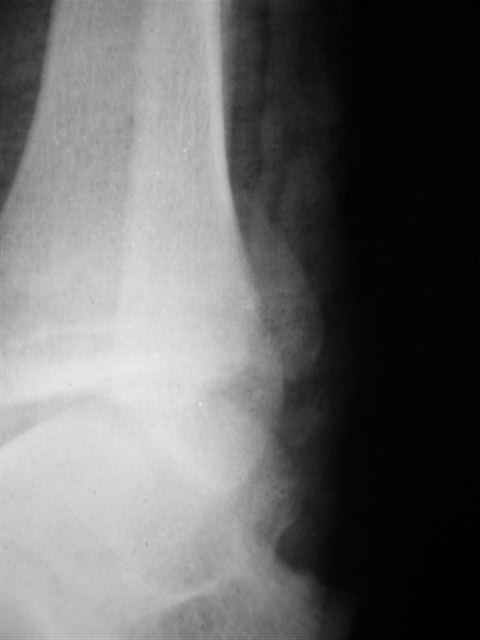

Спасибо за комментарии. Травма тяжелая с проблематичным прогнозом для функции коленного сустава( изначально травма разгибательного аппарата с последующим частичным некрозом собственной связки надколенника и о обнажением рефиксированного фрагмента бугристости большеберцовой кости, дефектом центрального отдела суставной поверхности большеберцовой кости и медиального отдела капсулы сустава).

В первом письме я упомянул о закрытом повреждении правого голеностопного сустава, эверсионно-пронационный механизм травмы - перелом внутренней лодыжки( поперечный, на уровне суставной щели) и отрывной перелом бугорка Chaput. После обработки открытых переломов бедра и большеберцовой кости в эту же сессию перелом внутренней лодыжки фиксировал двумя расходящимися спицами, бугорок Chaput двумя тягловыми винтами 3,5 мм. Раны заживают благополучно. Учитывая повреждение наружной группы мышц, активное разгибание в голеностопном суставе ограничено. Пассивная + пассивно-активная мобилизация голеностопного сустава с физиотерапевтом.